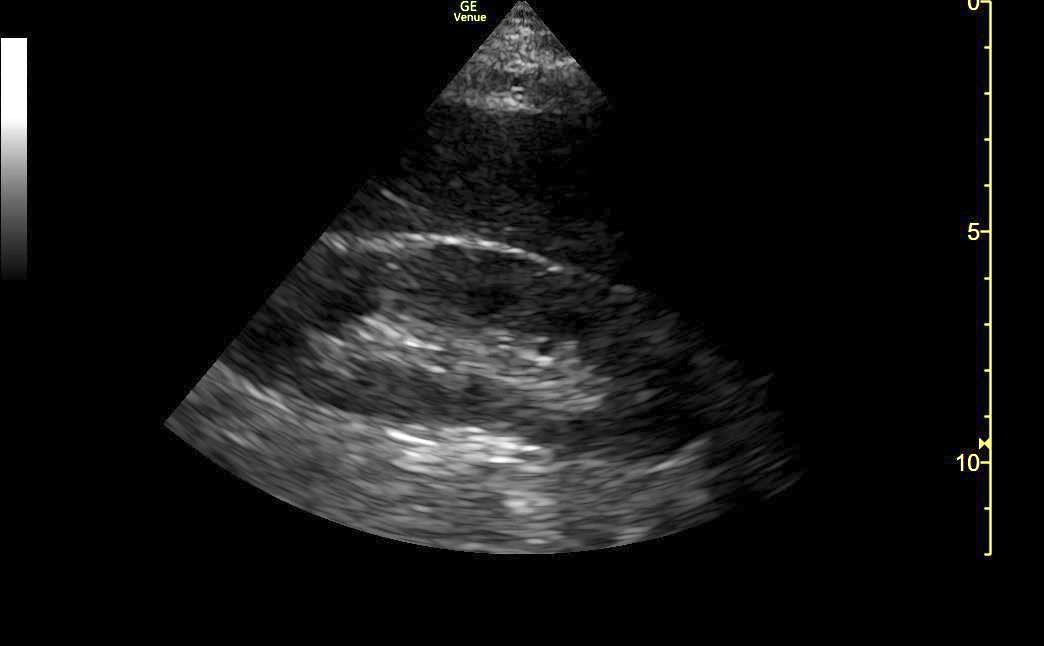

Only subxiphoid window was available:

LV and RV hypertrophy, Moderately ⬇️ LVEF, normal RV function, No tamponade, No RV Failure

These findings strongly argue against:

🔷 Right HF / PAH

🔷 Obstruction (Tamponade, PE)